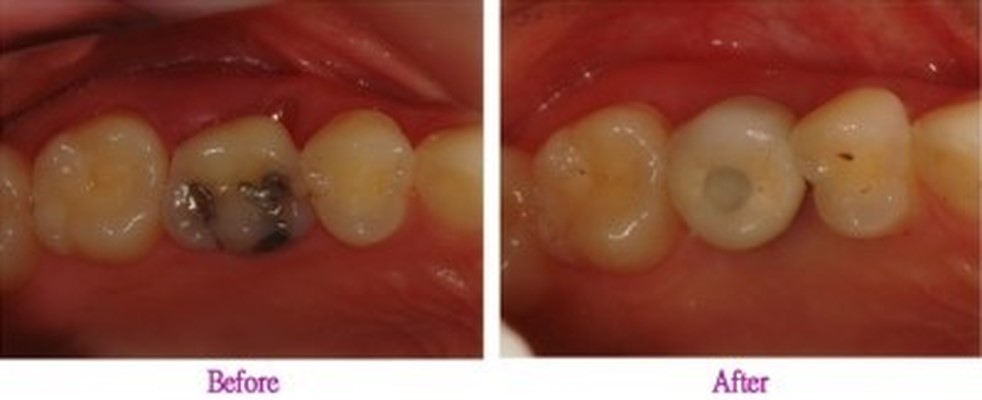

02 심하게 시행된 충치에 의해 치아를 발치 해야 하는 분